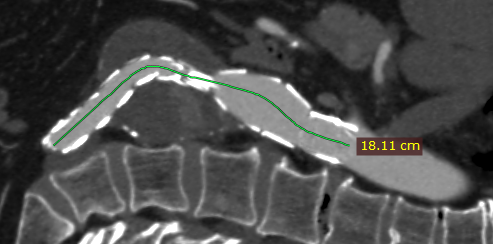

开放多边形示例

绘制完成后,将显示所绘路径的总长度。